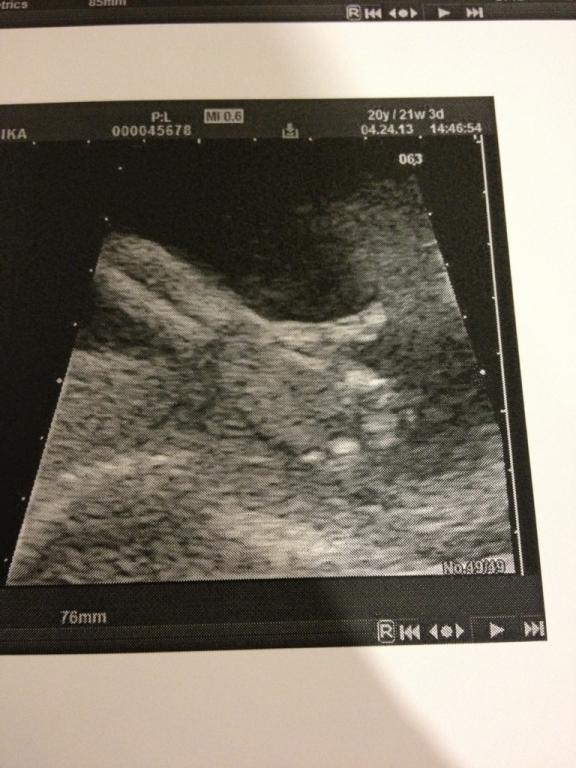

We're at about 9 weeks ourselves, I wish you luck in a complication free pregnancy.No E30 ClubOriginally posted by MrBurgundyAnyways, mustangs are gay and mini vans are faster than your car, you just have to deal with that.Comment